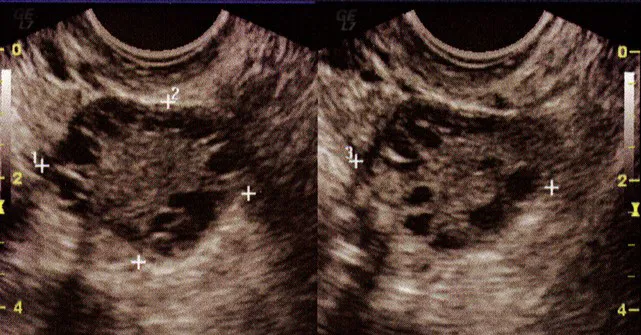

1. 多嚢胞卵巣症候群(PCOS)

ホルモンのバランスがくずれて排卵がうまくいかず、卵巣に小さな卵がたくさんたまった状態です。これにより月経不順や不妊の原因となります。PCOSの診断は超音波検査と血液検査によって行われます。

超音波検査

基本のスクリーニング検査として必須の検査です。通常、プローべという細い器具を腟から挿入して検査を行います。子宮や卵巣の大きさ、形、腫瘤(しゅりゅう)の有無などを確認します。

子宮の内膜や卵子のもとになる卵胞は、月経周期に伴って変化するため、複数回に分けて検査する場合もあります。